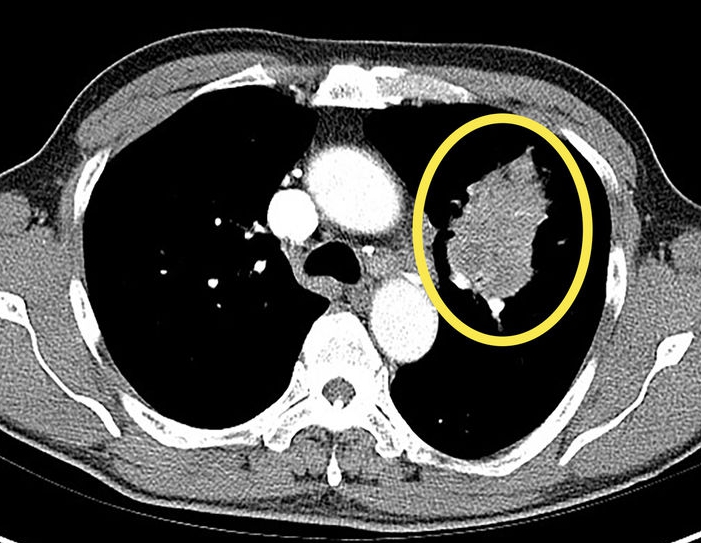

그 결과 ‘만성 폐질환’ 유무가 비흡연자 폐암 발병의 가장 강력한 위험인자로 확인됐다. 흡연 경험이 없더라도 만성폐쇄성폐질환(COPD), 폐결핵 등의 병력이 있는 경우 폐암 발병 위험이 대조군 대비 2.91배 높았다.

특히 만성폐쇄성폐질환(COPD)를 앓고 있는 환자의 경우, 폐암에 걸릴 위험이 7.26배까지 치솟았다. 연구팀은 폐에 지속되는 만성적인 염증 반응이 비흡연자의 폐암 발병에 기여했을 가능성을 제시했다.